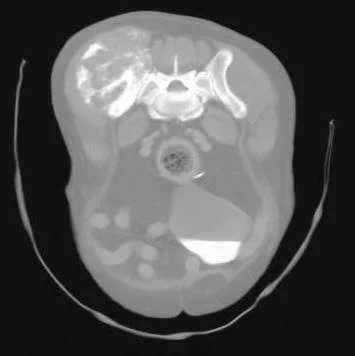

Survey radiographs may be sufficient for the diagnosis of pelvic tumors, but advanced imaging (CT or MRI scans) is preferred to determine tumor location, the extent of the tumor, and for surgical planning. Biopsy is rarely necessary as treatment options are not changed by a knowledge of the tumor type.

Abdominal and thoracic CT scans are recommended to assess for metastasis to the sublumbar lymph nodes, intra-abdominal organs,  and lungs. Alternatively, abdominal ultrasonography and three-view thoracic radiographs can be used to assess for the presence of metastatic disease.